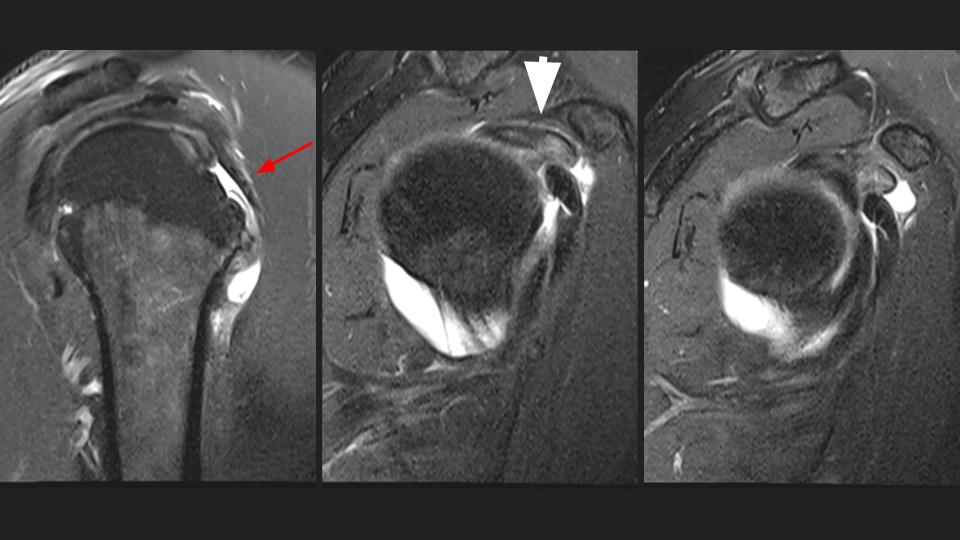

58M shoulder and upper arm pain x 4 weeks

There is a complete tear of the intraarticular long head biceps tendon (LHBT). The intraarticular remant is displaced into the superior subscapular recess and the torn retracted tendon is distal to the pec major insertion (bue arrow) in the mid upper arm (white arrow). Note the delaminating tear of the subscapularis tendon (red arrow). There is moderate supraspinatus tendinosis without tear (not shown).